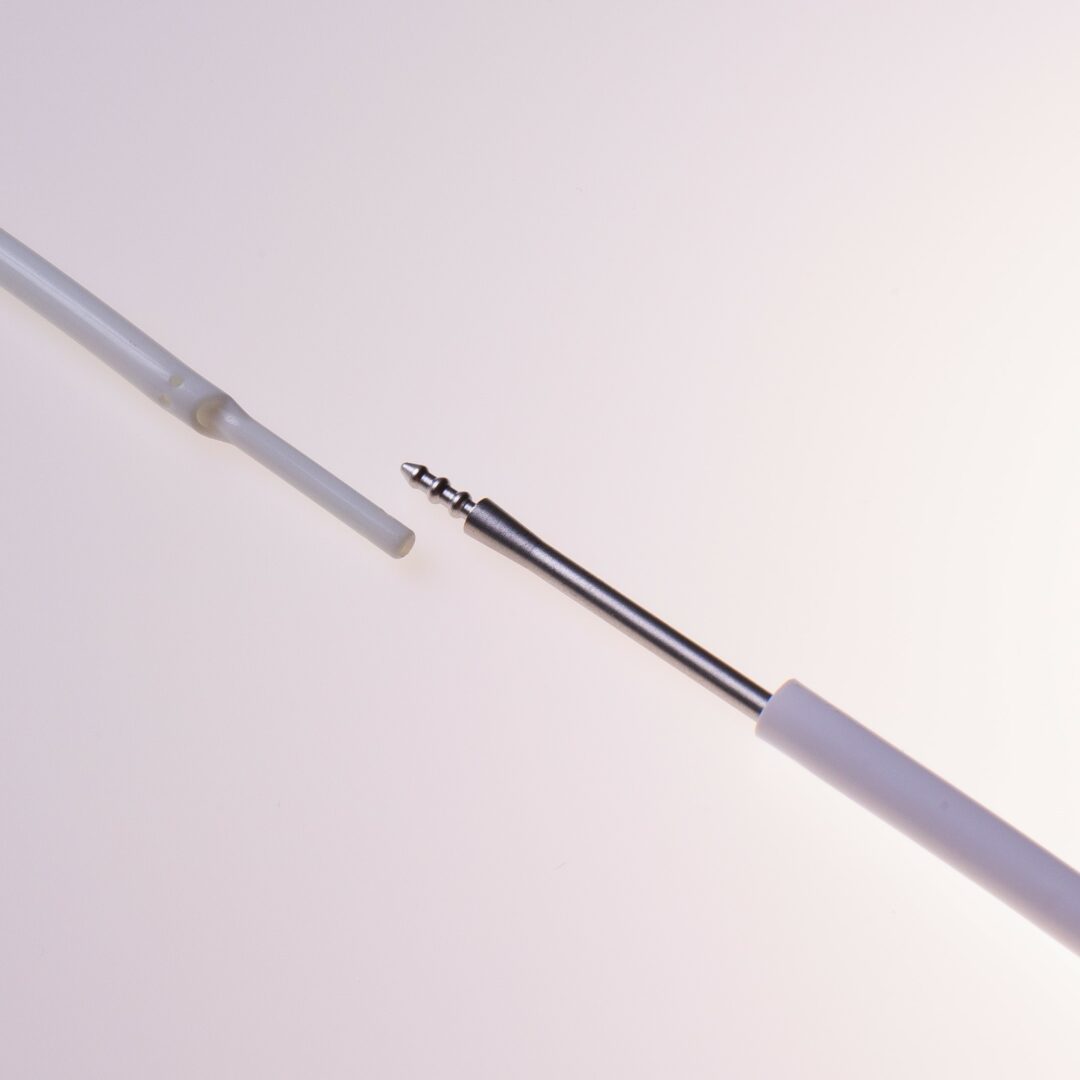

Tip Design

Der HFS Hemo Flow® verfügt über ein „Tap Tip“ Spitzendesign.

Der HFS Hemo Flow® wird antegrad untertunnelt. Die Einführung in das Gefäß erfolgt über eine Splitkanüle mit Schleuse.